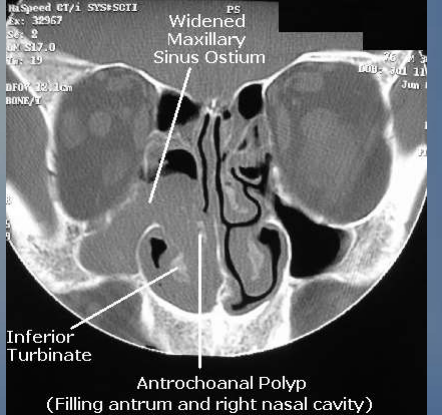

pólipo de Killian o antrocoanal características morfológicas (dónde y cómo se presenta y extensión)

dd de pólipo de Killian

al ser unilateral–> neoplasia nasosinusal

Consecuencia más importante de la sinusitis/patogenia

Obstrucción del osteum sinusal–> éstasis de drenaje –> acumulación de moco –> disminuye pH–> disminuye O2 –> anaerobio–> sobreinfección bacteriana–> inflamación–> alteración ciliar–> acumulación de moco